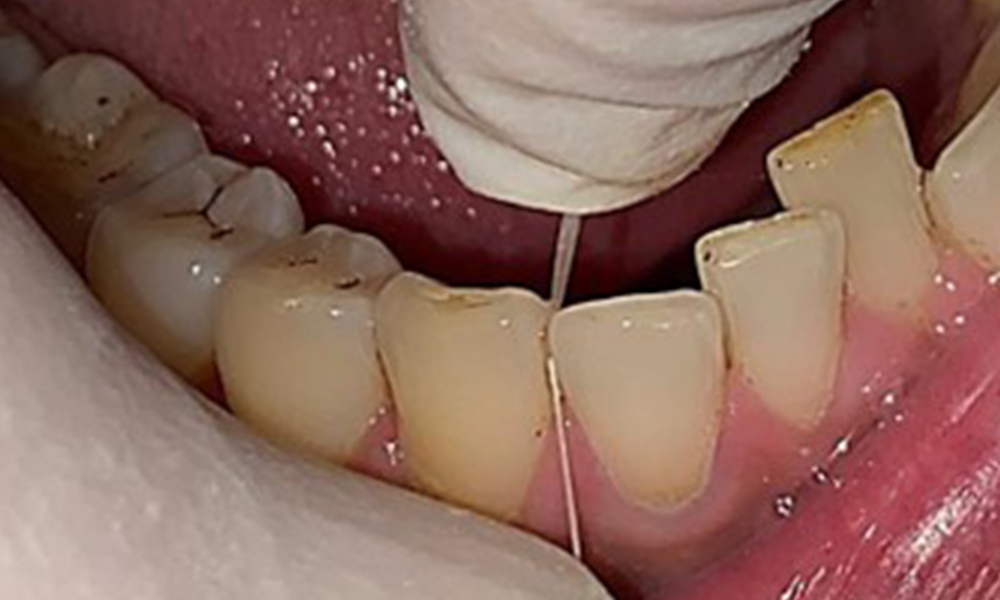

The patient has full dentition with a total of 28 teeth. There were noteworthy erosions and attritions. (Fig. 4, Fig. 5). Due to bruxism, the patient has been wearing a splint with an adjusted bite block at night for many years. The erosions were caused by long-term consumption of isotonic beverages. No periodontal bone loss or active caries were observed.

Close-up view of teeth

Fig. 5: Close-up view of teeth 45 to 47. The green arrows show dental attrition and erosions of the buccal cusps with partial enamel loss, © Dr R. Krapf